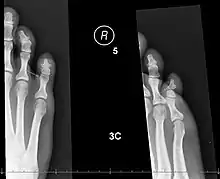

| X-rays of fractures of the proximal (left) and distal (right) phalanges in the little toe. | |

The AO Foundation/Orthopaedic Trauma Association (AO/OTA) classification generates numeric codes for describing broken toes.[8] They run 88[meaning a fracture of the phalanges].[number-code of toe, with the big toe=1 and the little toe=5].[number-code of phalanx, counting 1-3 outwards from the foot].[number-code of location on the bone, with 1 being the inner end, 3 the outer, and 2 in-between].[8] So, for instance, 88.1.2.1 means a fracture to the big toe's innermost bone, at the proximal end.[8][9] A letter can be added to describe the fracture pattern.[9]